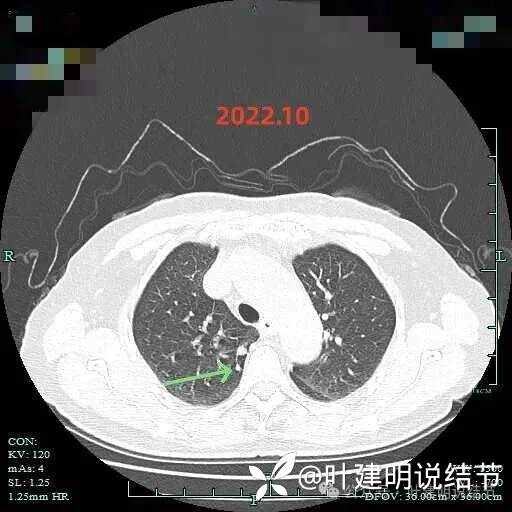

病灶出现,有磨玻璃成分,有血管进入与穿行,血管略有增粗。

混合密度,实性成分明显,微小血管进入明显,整体轮廓清楚,瘤肺边界清楚。

边缘有少许毛刺,实性部分密度较高,牵拉胸膜,边缘少许磨玻璃成分。

边缘区域有磨玻璃成分,实性部分密度主,紧贴胸膜。

边缘淡磨,血管走向病灶。

右上实性结节表面光滑,较圆,次病灶似卫星灶,密度过高,没有显著进展。